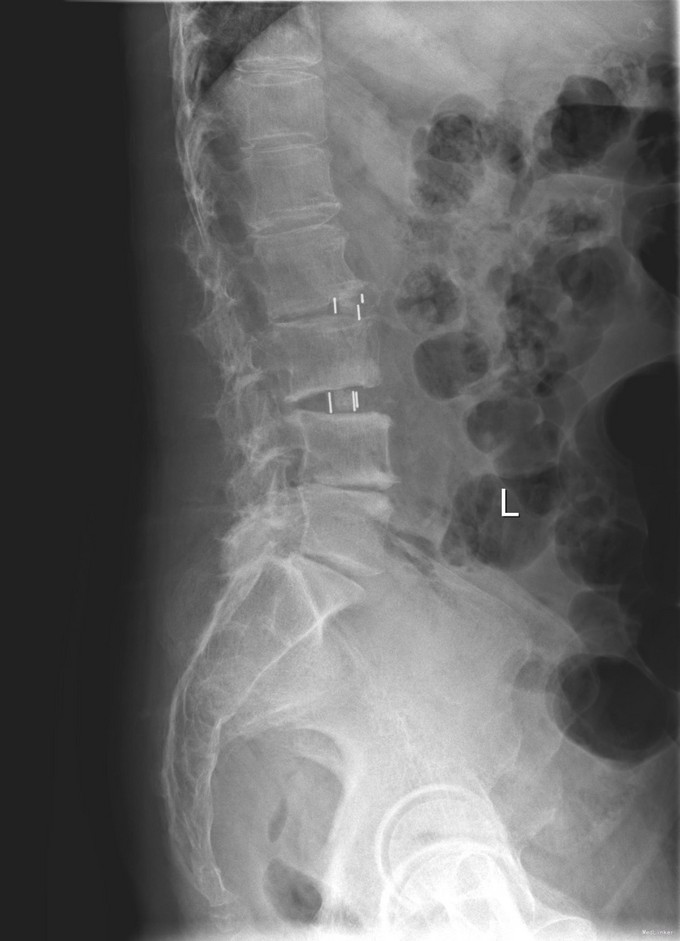

查体:脊柱无明显侧弯,腰背部无压痛,双下肢麻木酸痛,可牵连至脚跟。肌力肌张力可。腰部活动可,前屈后伸时感酸痛,无力。左侧直腿抬高试验阳性。 辅助检查:X线平片:腰椎侧弯前屈,L3椎体轻度滑脱,各椎间隙狭窄,腰椎退行性改变。 MRI:L4-5,L5-S1椎间盘膨出,L2-3,L3-4,L5-S1椎间隙狭窄,S2-3水平骶管内蛛网膜囊肿,腰椎序列不稳定,生理曲度局部后凸。

诊断:1 脊柱侧弯 伴不稳 2椎管狭窄 治疗: 前期微创腰椎侧路融合手术+后期 微创后路经皮内固定